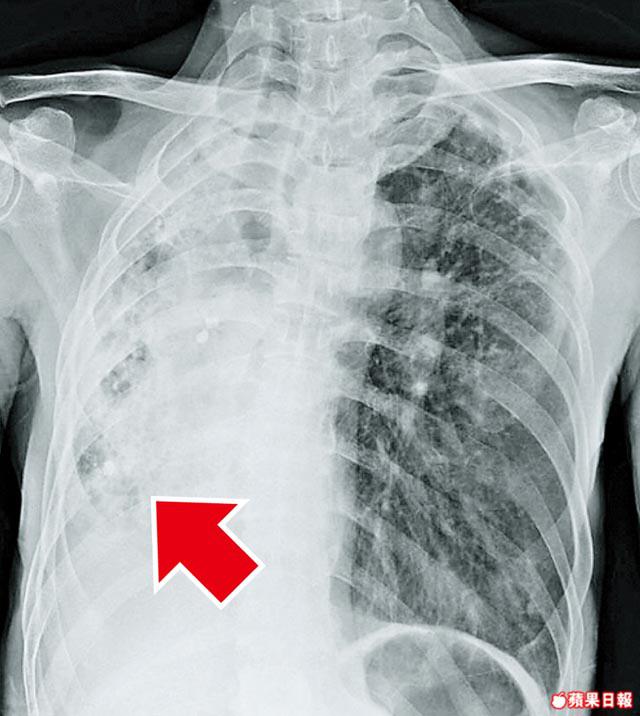

大量咳血是指24小時內咳出500毫升血,或持續多天每天咳出約100至200毫升血;令病人出現呼吸道阻塞,嚴重可引致缺氧,死亡率高達50%以上。曾有病人數小時內咳出數公升血。大量咳血主要是曾患支氣管擴張及肺癆引起的後遺症,病人會有不正常血管增生,容易出血。大部份病人是支氣管動脈出血。

聯合醫院於2000至06年以支氣管動脈栓塞術,治療251名大量咳血病人,他們平均約67歲,於24小時內平均咳血約300毫升,約30%人要接受深切治療。95%病人手術後即時止血,有55%病人手術後5年沒有再咳血,有5%病人會有輕微併發症,如發燒及傷口痛。少數病人因出血情況嚴重,要切除部份受破壞肺葉,以防日後復發。